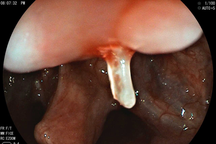

Khi chạm vào ổ áp xe, phát hiện dị vật là đoạn xương cá nhọn, dài 4cm. Cả ekip rất ngạc nhiên.

Mảnh xương cá được gắp ra (Ảnh: Bệnh viện cung cấp).